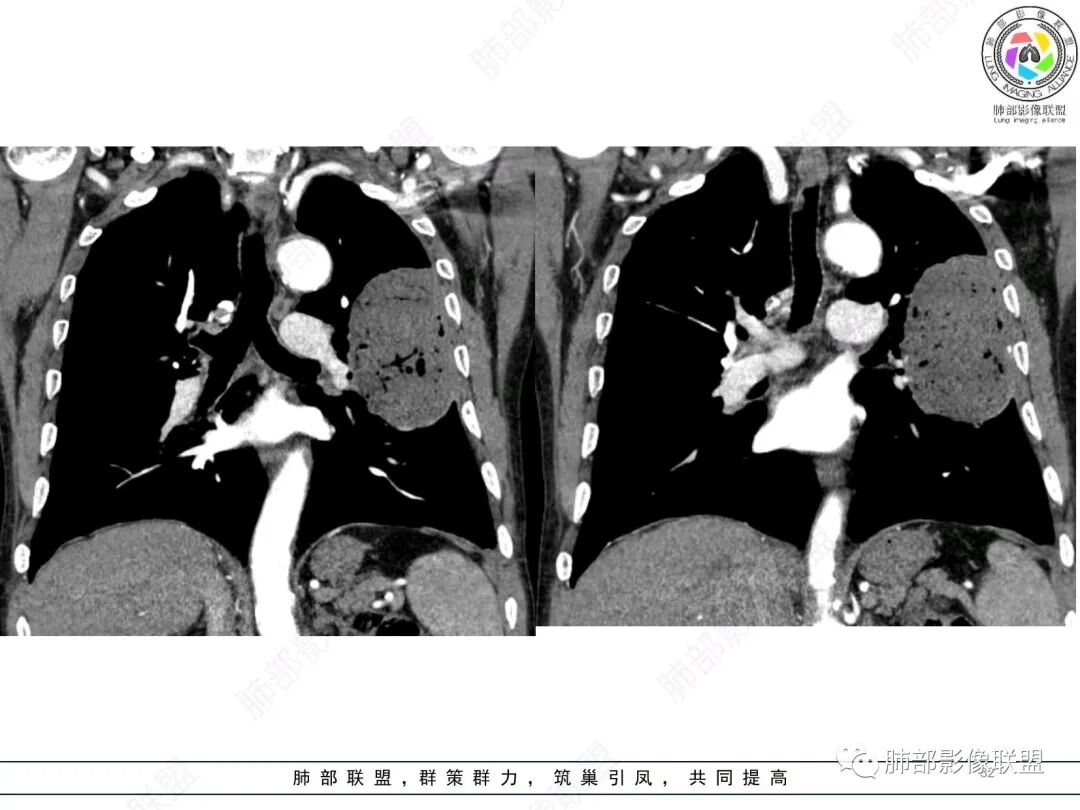

左肺上叶大肿块,膨胀性生长,边界清,密度较低,见部分坏死区,强化弱,肿块见支气管充气V扩张征,分布僵直,枯树枝特点,另一个重要特点血管造影征,淋巴瘤,肿块长轴与胸膜平行,与隐球菌鉴别,隐球荚膜抗原检查,明确诊断经皮肺穿刺。另胸膜钙化(问诊既往有无患胸膜炎病史)。

左肺上叶胸膜下肿块,宽基底与胸膜相连,跨叶裂,边缘清晰膨隆,其内支气管充气,部分扩张、僵直,无明显强化,血管造影征,考虑淋巴瘤,鉴别腺癌

左肺胸膜下巨大占位,跨叶裂,宽基底与胸膜相连,胸膜钙化,平扫密度较低,强化不明显,可见内部血管显影,支气管充气征和扩张,考虑为恶性,倾向于淋巴瘤

左侧胸腔巨大肿块,跨叶生长,临近胸膜钙化,边缘模糊,可见支气管影,定位肺内,增强后轻度强化,边缘见血管影,考虑淋巴瘤,鉴别肉瘤

支持淋巴瘤,左上肺大肿块,有分叶,边缘光整,病灶内密度不均,可见支气管扩张征,增强后可见血管影征。周围肺野清晰。

左肺上叶肿块,宽基底与胸膜相连,跨叶裂,边缘清晰膨隆,可见小分叶,其内支气管充气,部分扩张、僵直,呈枯枝征,支气管达边征,增强无明显强化,可见血管造影征,考虑恶性病变,淋巴瘤,鉴别粘液腺癌。

大肿块,边缘光滑,深分叶

近端支气管堵塞、推移为主

部分类似于脐凹征

内部支气管扩张

肺动脉推移为主,边缘部分进入